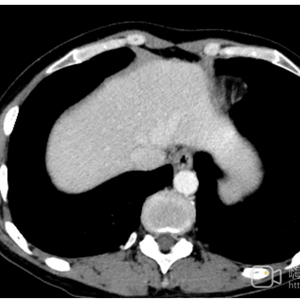

• 2023年2月5日行腹部CT检查(图1),提示胃壁增厚僵硬,以胃体为著,考虑胃癌(T4N3)。